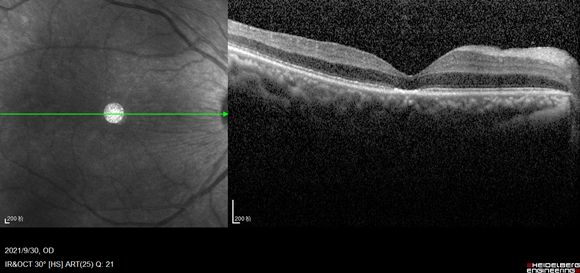

我很快为患者安排了手术。手术中,既要把球内异物完整的拿出来,又要不伤及眼内其他正常结构。手术需要首先将玻璃体切除干净,然后用特制的异物钳将异物取出眼外。异物所处的位置就在视神经旁,已经扎穿了视网膜并嵌入脉络膜中,距离视盘不到0.5mm,稍微操作不慎不仅会导致脉络膜大出血,还会伤及视神经从而造成视功能不可逆的损伤。玻璃体切除手术整个过程我需要保持一个姿势不动,本来就比较累,更别提是在青藏高原上完成这个手术,对体力和毅力都是巨大的考验。想起尼玛对我说过的话,我定了定神,吸着氧气顺利完成手术,将长度为7mm的异物从眼内完整取出,晶体和视网膜都未受到额外扰动,患者眼内填充的空气经过1周吸收后,矫正视力达到0.6。

术后复诊时,尼玛之前视物遮挡的症状完全解除,激动不已,连声说“谢谢韩医生,谢谢韩医生!扎西德勒!扎西德勒!”